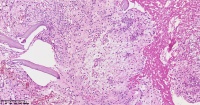

请教老师们这些巨细胞有什么临床意义?

性别

女

年龄

61岁

临床诊断

股骨头骨折

一般病史

标本名称

股骨头组织

大体所见

股骨头骨折处组织

多核吞噬细胞,有纤维素性坏死

是一种反应性改变。